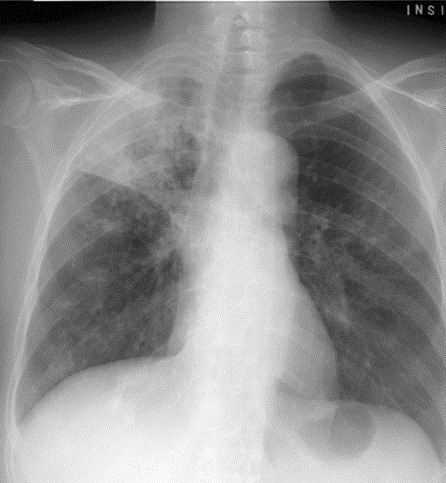

326) A 55 year old african-american man presents to your office with complaints of shortness of breath that has slowly progressed over the past several months. He also reports chest pain which in non-pleuritic in nature. He has lost about 10lbs weight in the past three months. He has changed several jobs but he currently works as a sales representative for a drug company. On examination, his temperature is 100F, Pulse 98/min, RR 20/min and Blood Pressure 100/60 mm HG. He is in mild distress due to shortness of breath. On chest examination, there is dullness to percussion over the right side of the chest. No masses are palpable. Laboratory investigations reveal WBC 8k/μl with normal differential, Hgb 10.5gm%, Platelets 550k/μl, Calcium 11.2gm% ( (Normal 8.9 to 10.5 mg%)

A chest-x-ray is shown below:

Which of the following element in the history would be most helpful in making a presumptive diagnosis of his presentation?

A) Smoking

B) Family history of Cancer

C) Bone pain

D) Flank pain and Hematuria

E) Previous Occupation